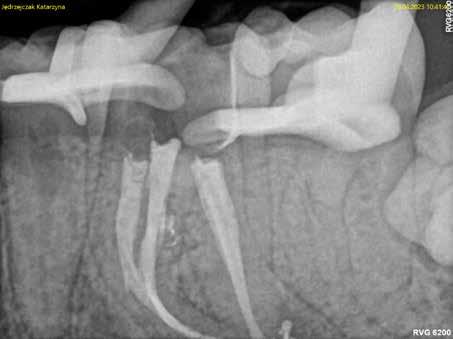

A páciens a jobb alsó első nagyőrlőfogából kiinduló közepes erősségű fájdalom miatt kereste fel a rendelőnket. Periapikális röntgen és CBCT-felvétel is készült. Mindkét felvétel a mesiobukkális gyökércsúcs körül található radiolucens elváltozás jelenlétét igazolta. Ezenfelül a mesialis gyökérben két betört eszközdarab is észlelhető volt. Az egyik a középső gyökéri harmadban a gyökérgörbület előtt volt megtalálható, a másik pedig kicsivel a gyökérgörbület után (12–13. ábra).

12. ábra: A kiindulási CBCT-felvételen jól látható a periapikális felritkulás. – 13. ábra: A kiindulási röntgenfelvételen látható a két betört eszközdarab.